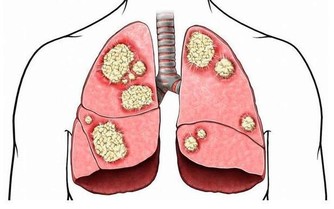

肝臟是人體最大的排毒器官,健康的肝臟可避免腹脹、便秘等麻煩,同時也起著調節血糖的重要作用。中醫常說:“養肝就是養命”,如果肝臟代謝不正常,人體所需的養分得不到及時供應,身體各個器官都無法正常工作。今天就帶著大家看看這9大隱蔽的“肝臟殺手”。